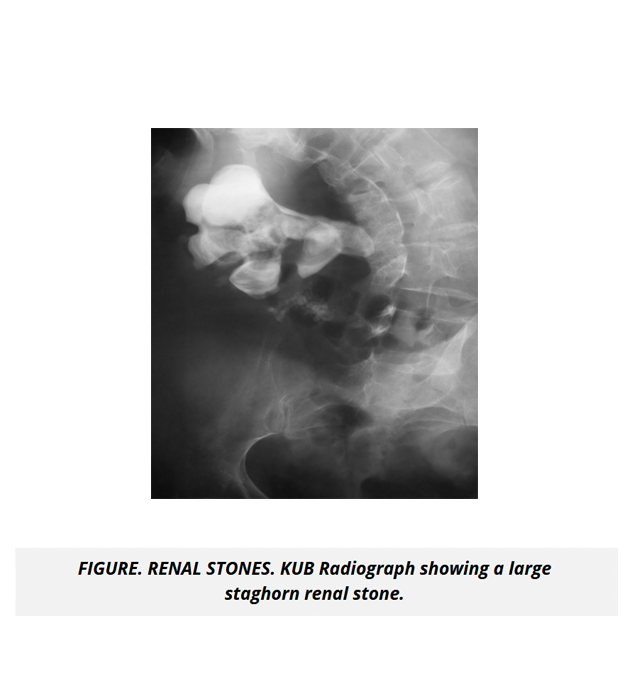

The course includes high quality radiological images and microscopic views highlighting normal and abnormal processes specific to renal and urinary diseases to give you a distinguished understanding of the application of concepts in clinical scenarios.

• Urolithiasis

• Tubular and Interstitial Disorders of the Kidney